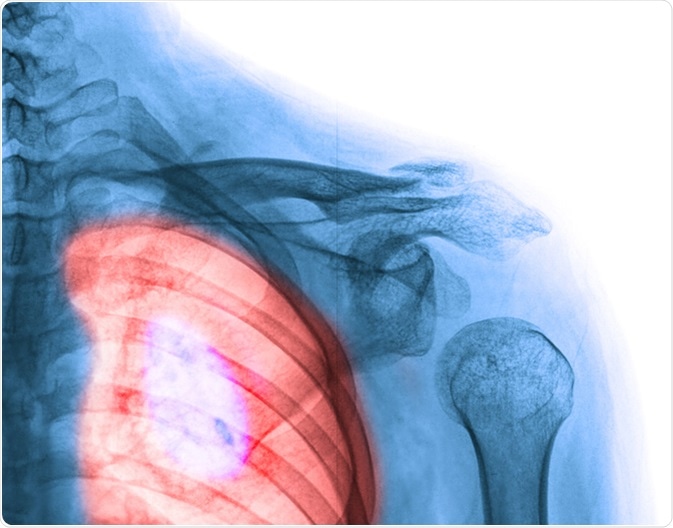

Lung cancer. Image Credit: Wonderisland / Shutterstock